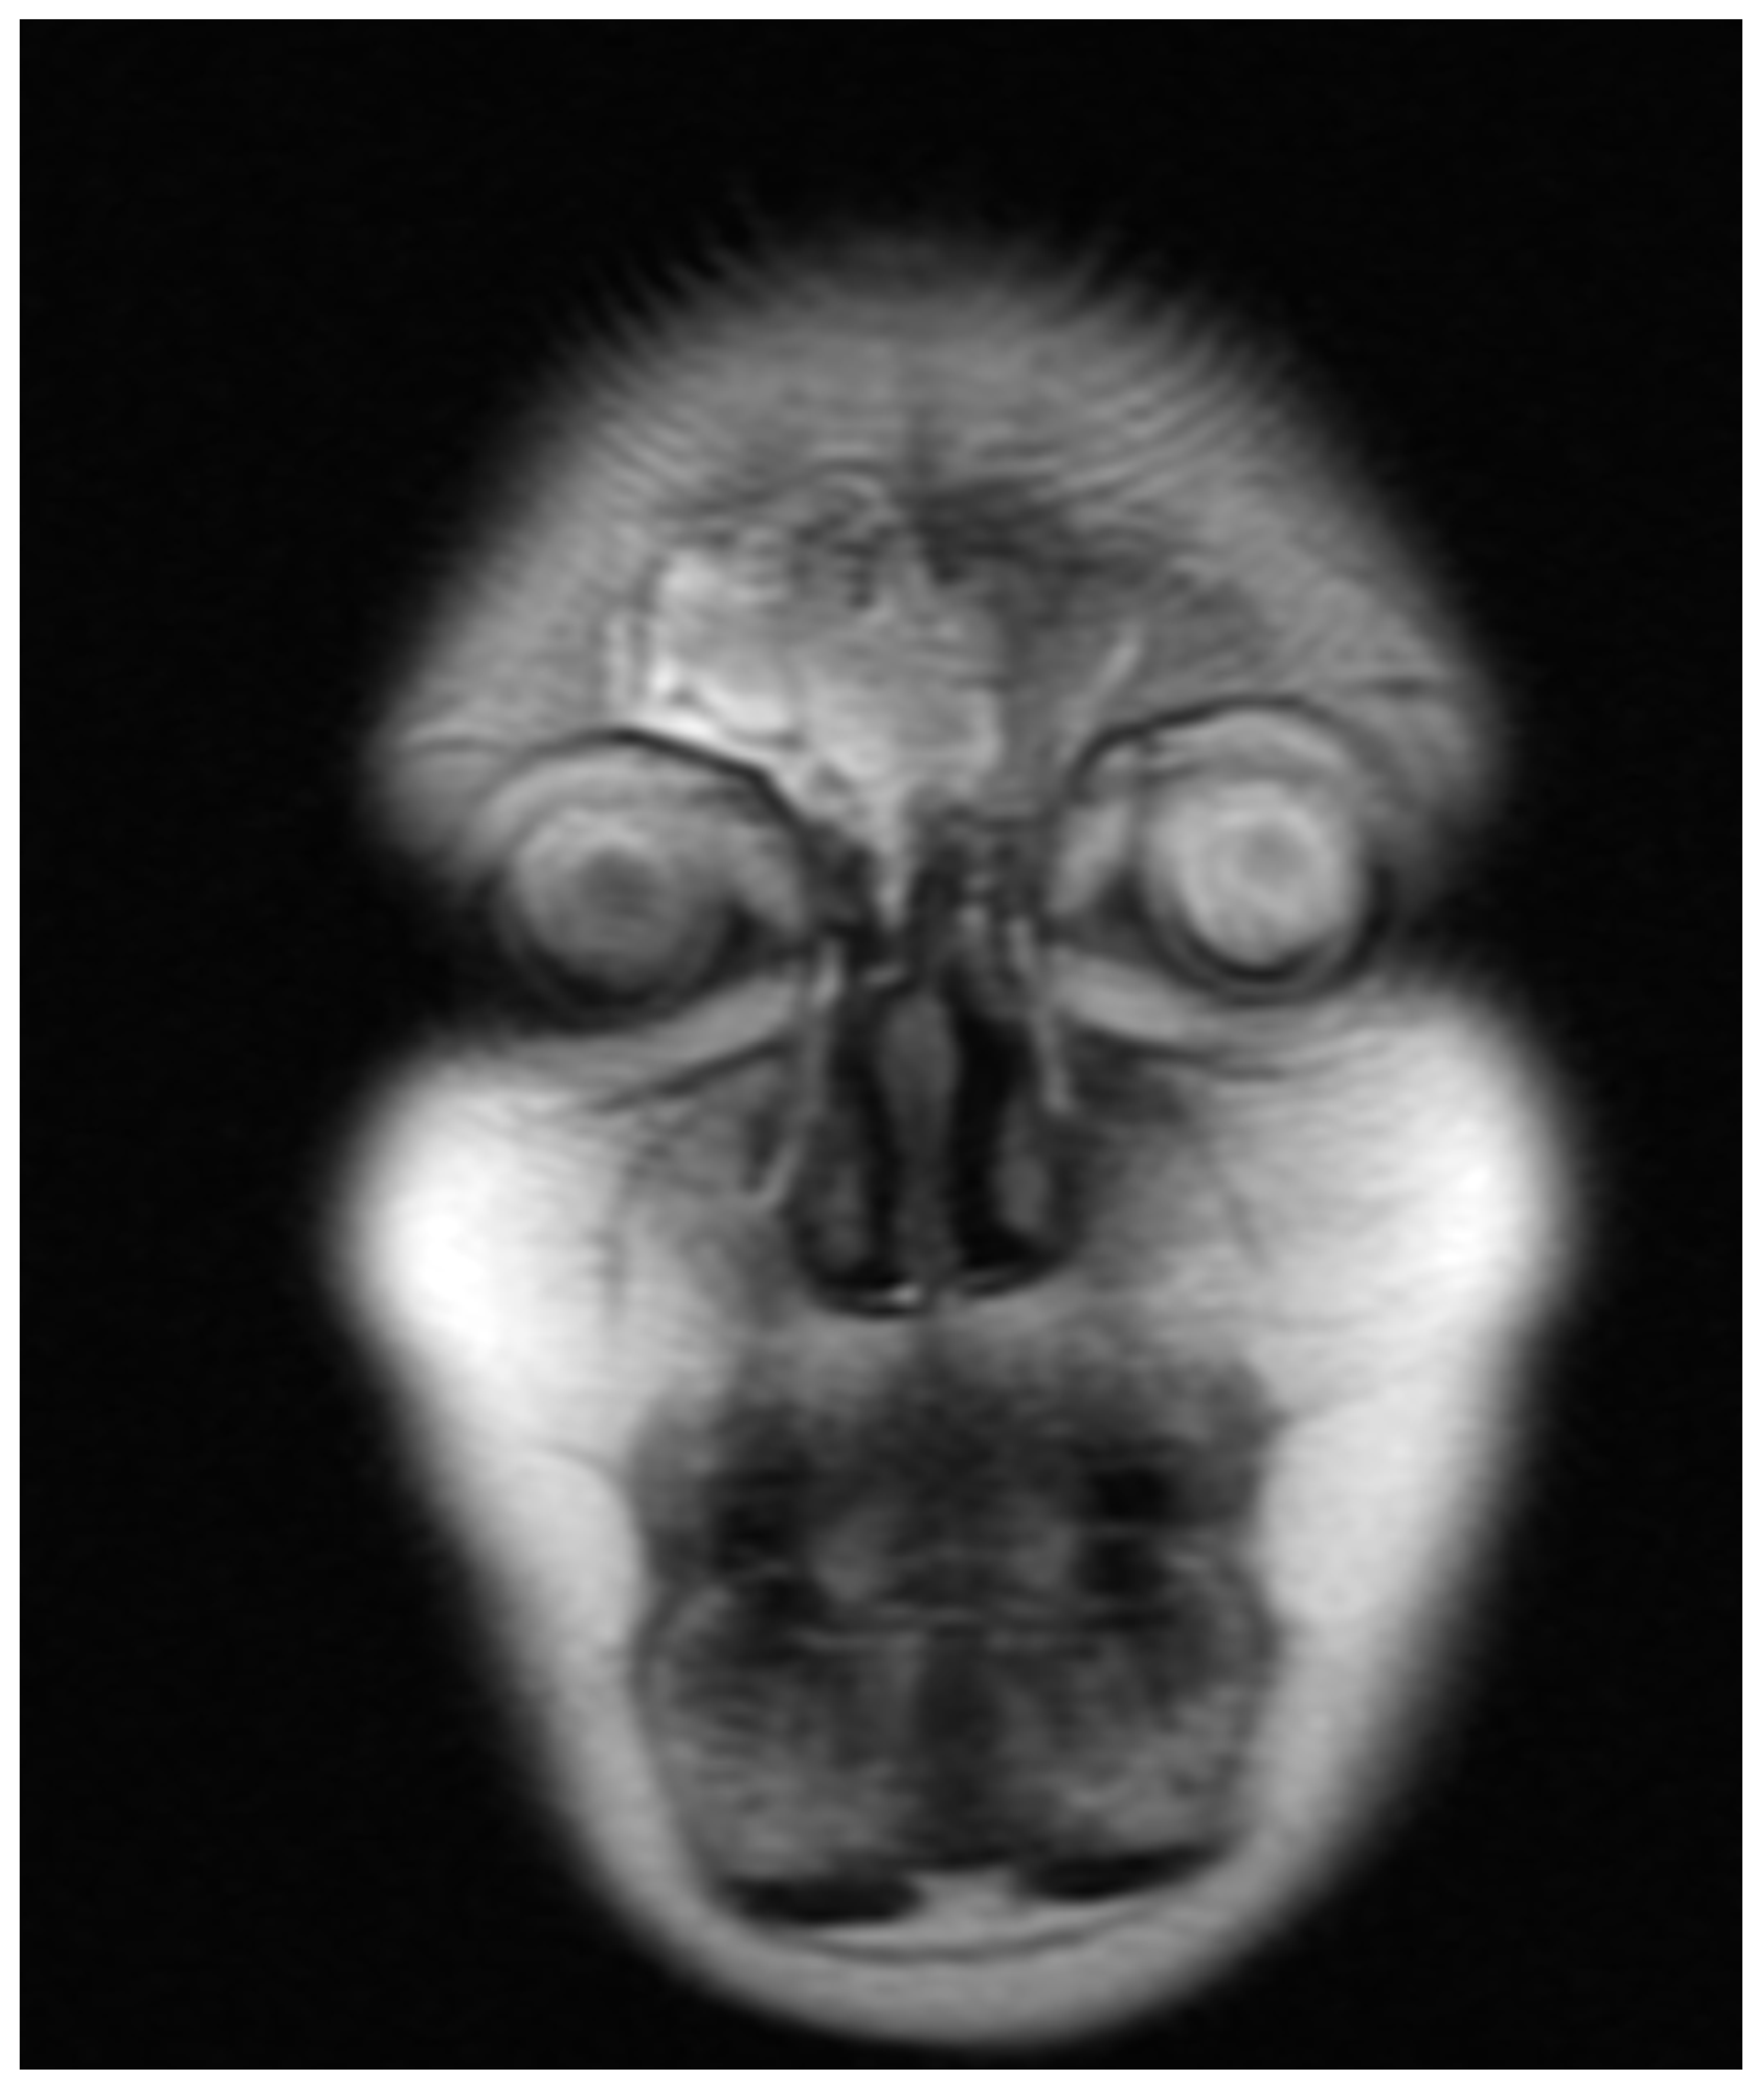

In November 2020, the patient presented with a sudden loss of vision in the LE limited to light perception due to the compression of the left optic nerve with inflammatory/granulomatous masses extending from the ethmoid (Figure 12). Methylprednisolone and immunoglobulins were administered intravenously. Due to the high activity of the disease and the high risk of vision loss in the RE, rituximab was introduced. Four weekly RTX infusions were given with a subjective improvement of vision. In the last week of the treatment, a fistula formed in the ethmoid lamina, causing the rhinorrhea of the cerebrospinal fluid through the right nasal passage (Figure 13). Subsequently, RTX treatment was complicated by the reactivation of opportunistic infections: CMV and HSV1 (high transaminases). Therefore, ganciclovir was introduced.

Figure 13. MRI of coronal plane with a massive lesion in the right ethmoid sinus cavity.